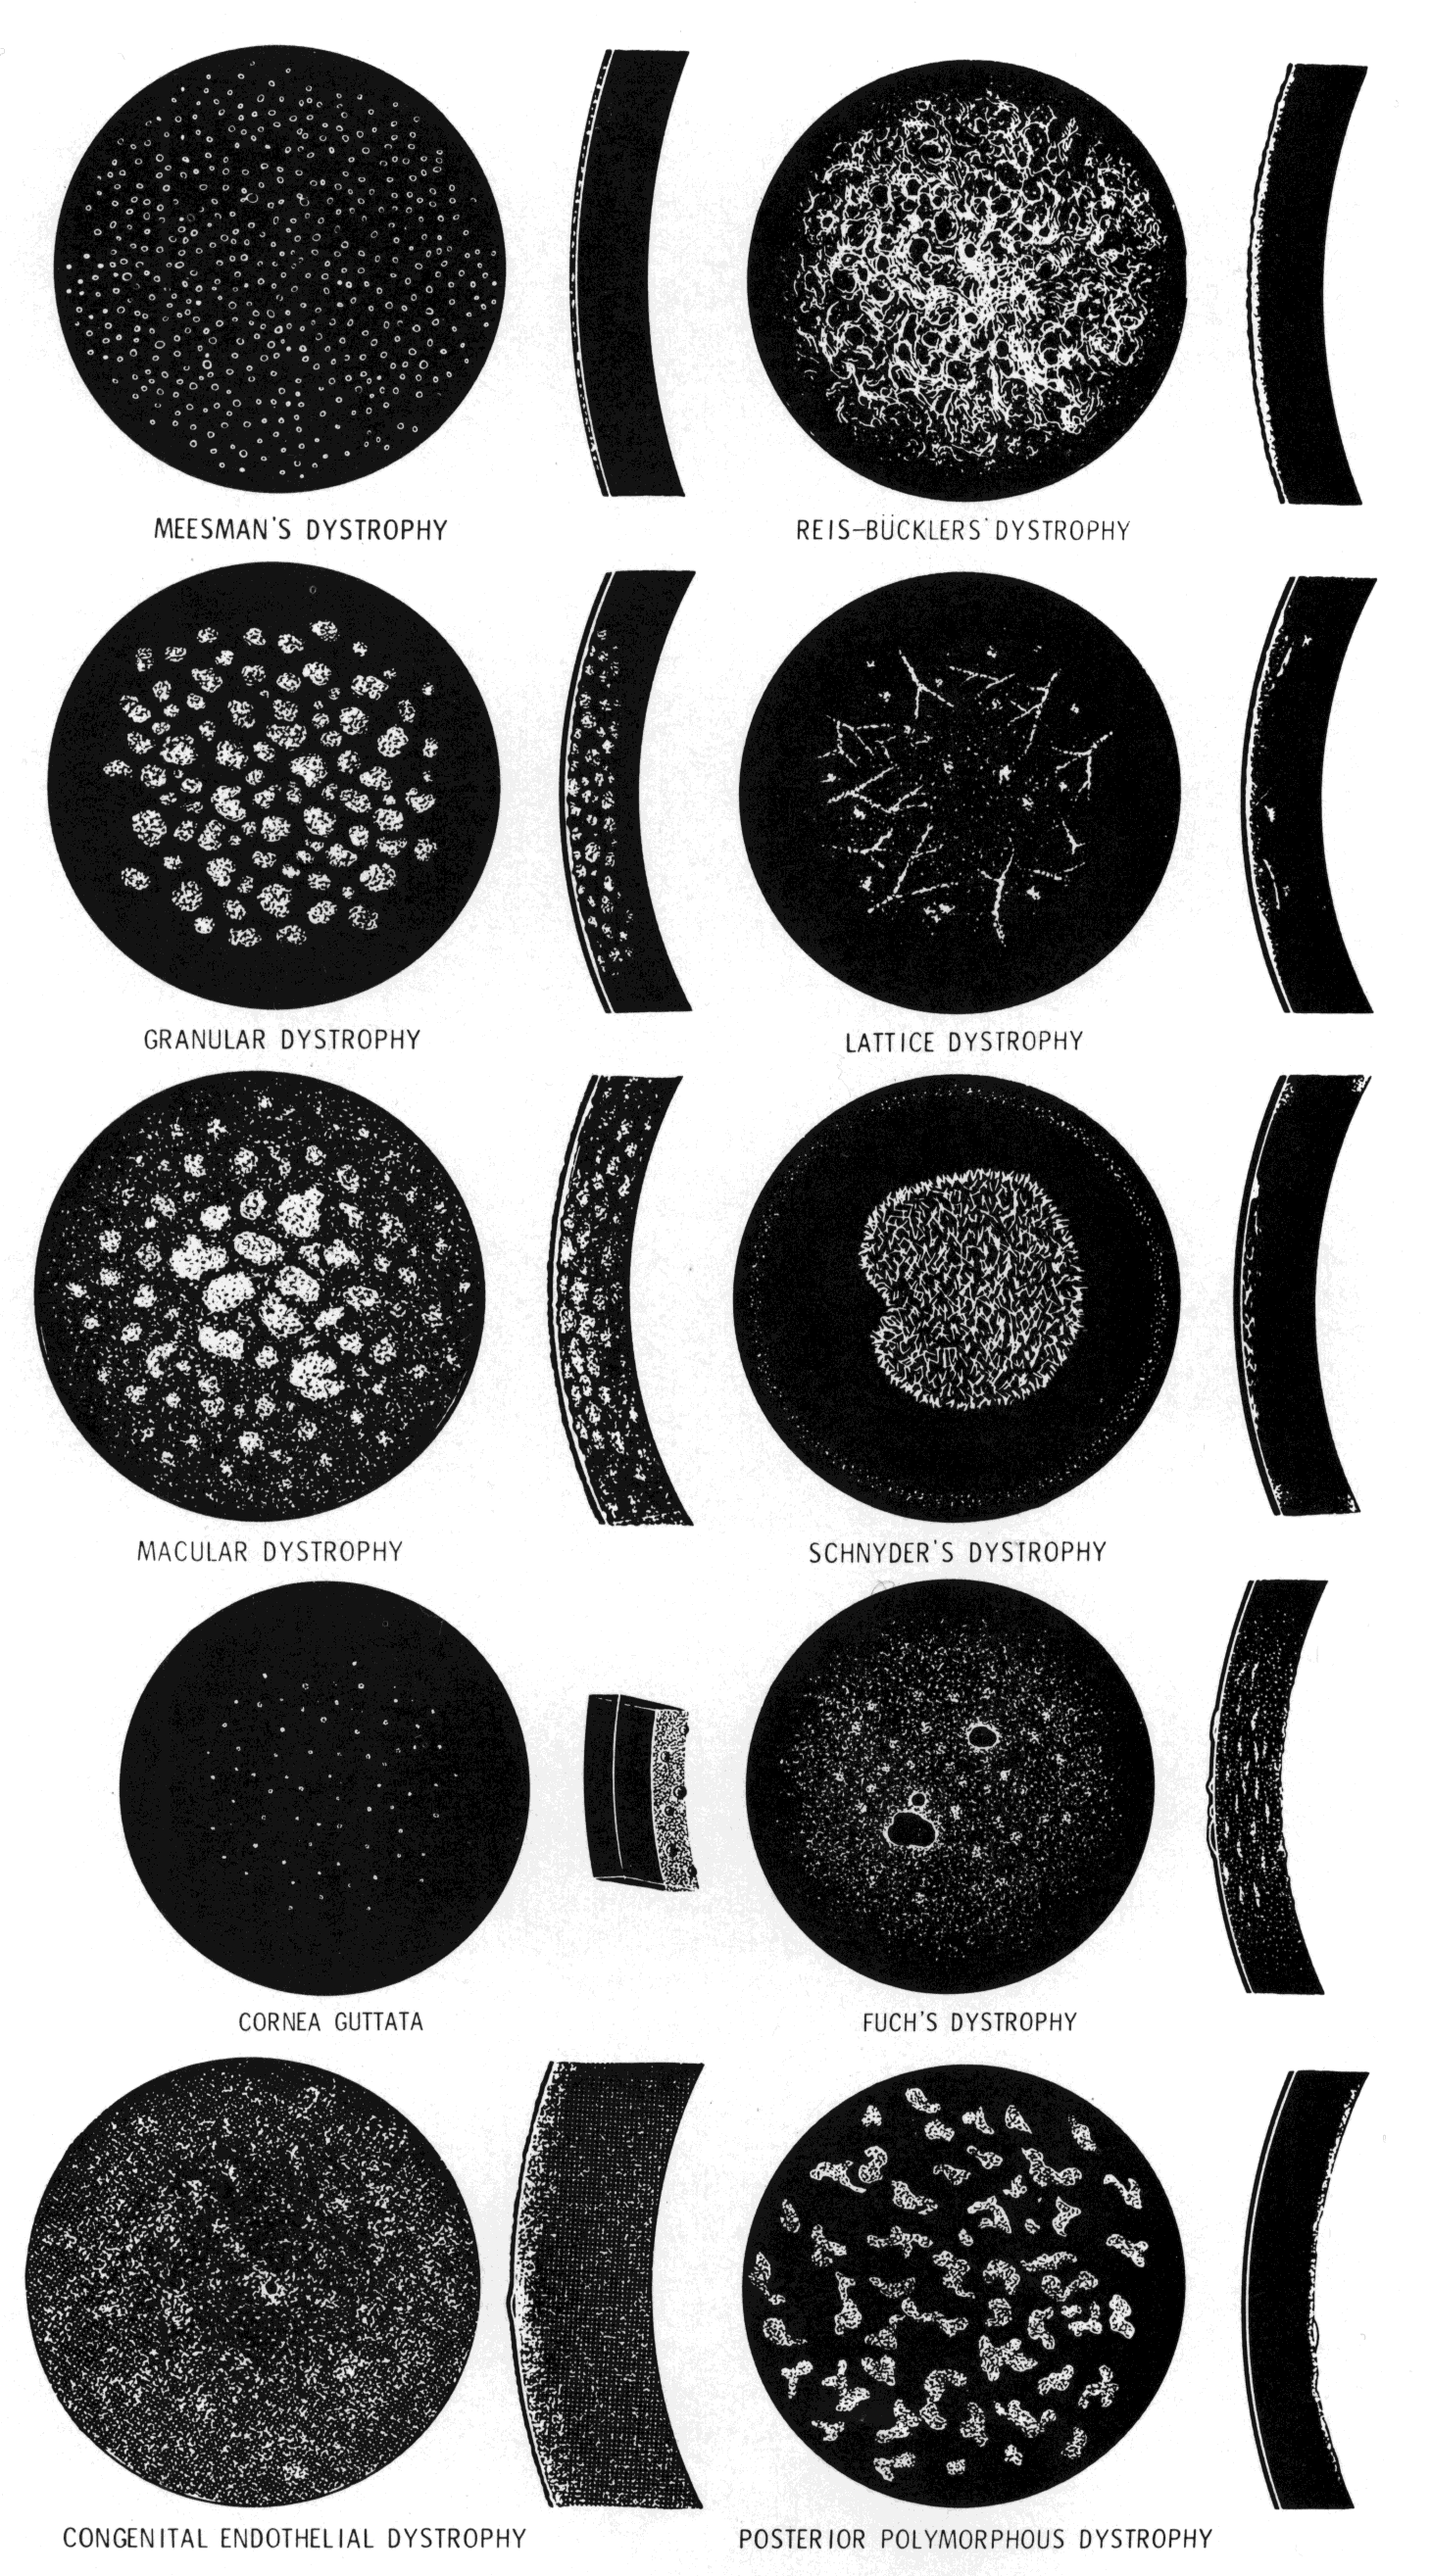

The anterior corneal dystrophies (Fig. 5) are confined to the epithelium, basement membrane, and, in some cases, Bowman's layer.

Fig. 5. Characteristic corneal changes in various types of corneal dystrophy. (Courtesy of A. Bron, MD. Goldberg M: Genetic and Metabolic Eye Disease, pp 283–285. Boston, Little, Brown & Co, 1974)